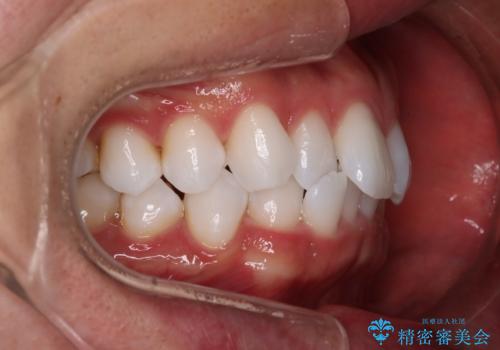

治療症例の内容

- 患者様

- 20代男性

- 矯正装置

- インビザライン

- 治療期間

- 1年

- 治療回数

- 5-10回

- 治療計画

- がたつきが気になるとの事で来院されました。

目立たない装置で費用も抑えたいとの希望があったため、インビザラインにて治療をすることとなりました。

上下顎ともにIPR(歯と歯の間を削る処置)を行い歯並びを整える治療計画を立てました。

治療当初は、計画通りに治療が進むか心配でしたが、しっかりマウスピースを使用していただいたことで

治療期間も長引くことなく歯並びを綺麗に改善することが出来ました。

患者様の希望もあり、前歯の微調整で1回リファイメント(マウスピースの再発注)を行いました。

患者様の希望に沿う治療を提案することができ良かったと思います。